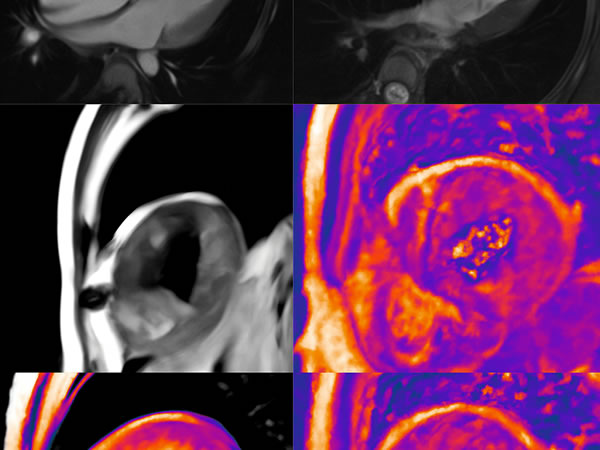

Patología aneurismática de cayado aórtico y aorta descendente torácica en paciente con dolor precordial atípico